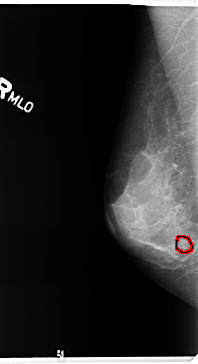

B_3363_1.RIGHT_MLO

RIGHT_MLO LINES 4720 PIXELS_PER_LINE 2568 BITS_PER_PIXEL 12 RESOLUTION 50 OVERLAY

FILE: B_3363_1.RIGHT_MLO.OVERLAY

TOTAL_ABNORMALITIES 1

ABNORMALITY 1

LESION_TYPE CALCIFICATION TYPE PLEOMORPHIC DISTRIBUTION CLUSTERED

ASSESSMENT 4

SUBTLETY 3

PATHOLOGY BENIGN

TOTAL_OUTLINES 1

BOUNDARY